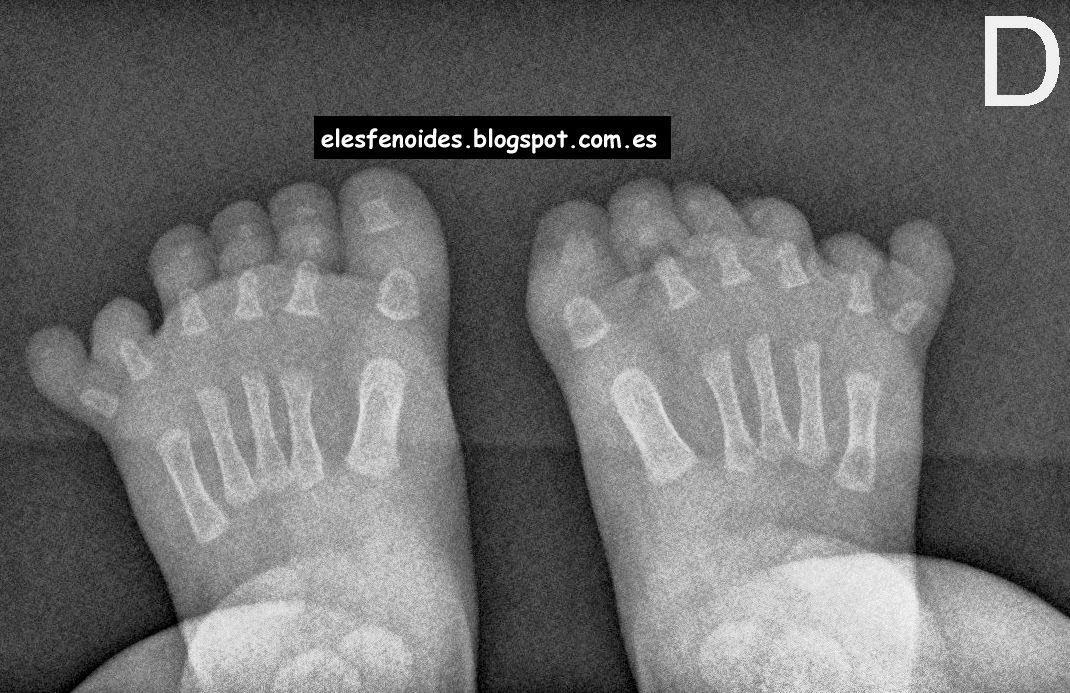

Rx de ambos pies dos posiciones.

Hexadactilia postaxial bilateral sin observarse fusión ósea ni otros hallazgos de interés.

No se identificaron otras alteraciones esqueléticas.